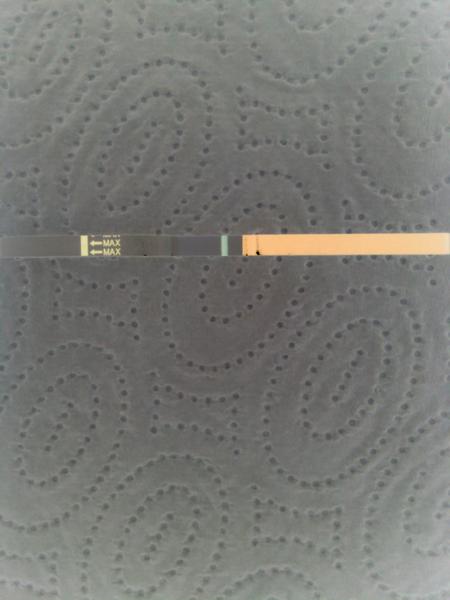

Těhotenský test. Dávám fotku. Co myslíte?

dnes jsem si dělala testík...

Udělal jsem radši ještě jeden - jmenuje se ForYou... Tam se objevil slabý duch, ale až tak za 3minuty! Šla jsem ven se psi a když jsem se vrátila, tak duch byl silnější...no ale to bylo skoro po půl hodině!

Tak nevim ... ☹ Dávám fotku, skuste posoudit...